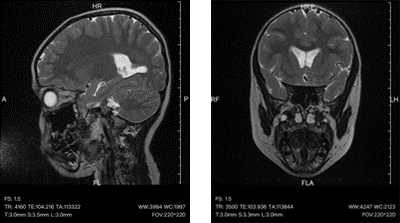

5岁6个月的男孩果果(化名)身高仅104cm,比同龄儿童矮11cm,体重17kg,还伴有“双眼内斜视”。曾在当地医院按照“肠道功能紊乱导致的营养不良”给予益生菌及补钙等治疗无果,后来转诊至烟台山医院儿童保健科儿童生长发育门诊,经嵇玉华主任医师检查发现:生长激素明显偏低、甲状腺功能异常,头颅MRI在颅内鞍区发现了一个直径约6cm的“爱心形”颅咽管瘤——这个深藏颅内的肿瘤,正是遏制孩子生长的幕后黑手。

头颅磁共振影像

头颅MRI:首选检查,可清晰显示肿瘤大小、位置及与周围结构的关系;